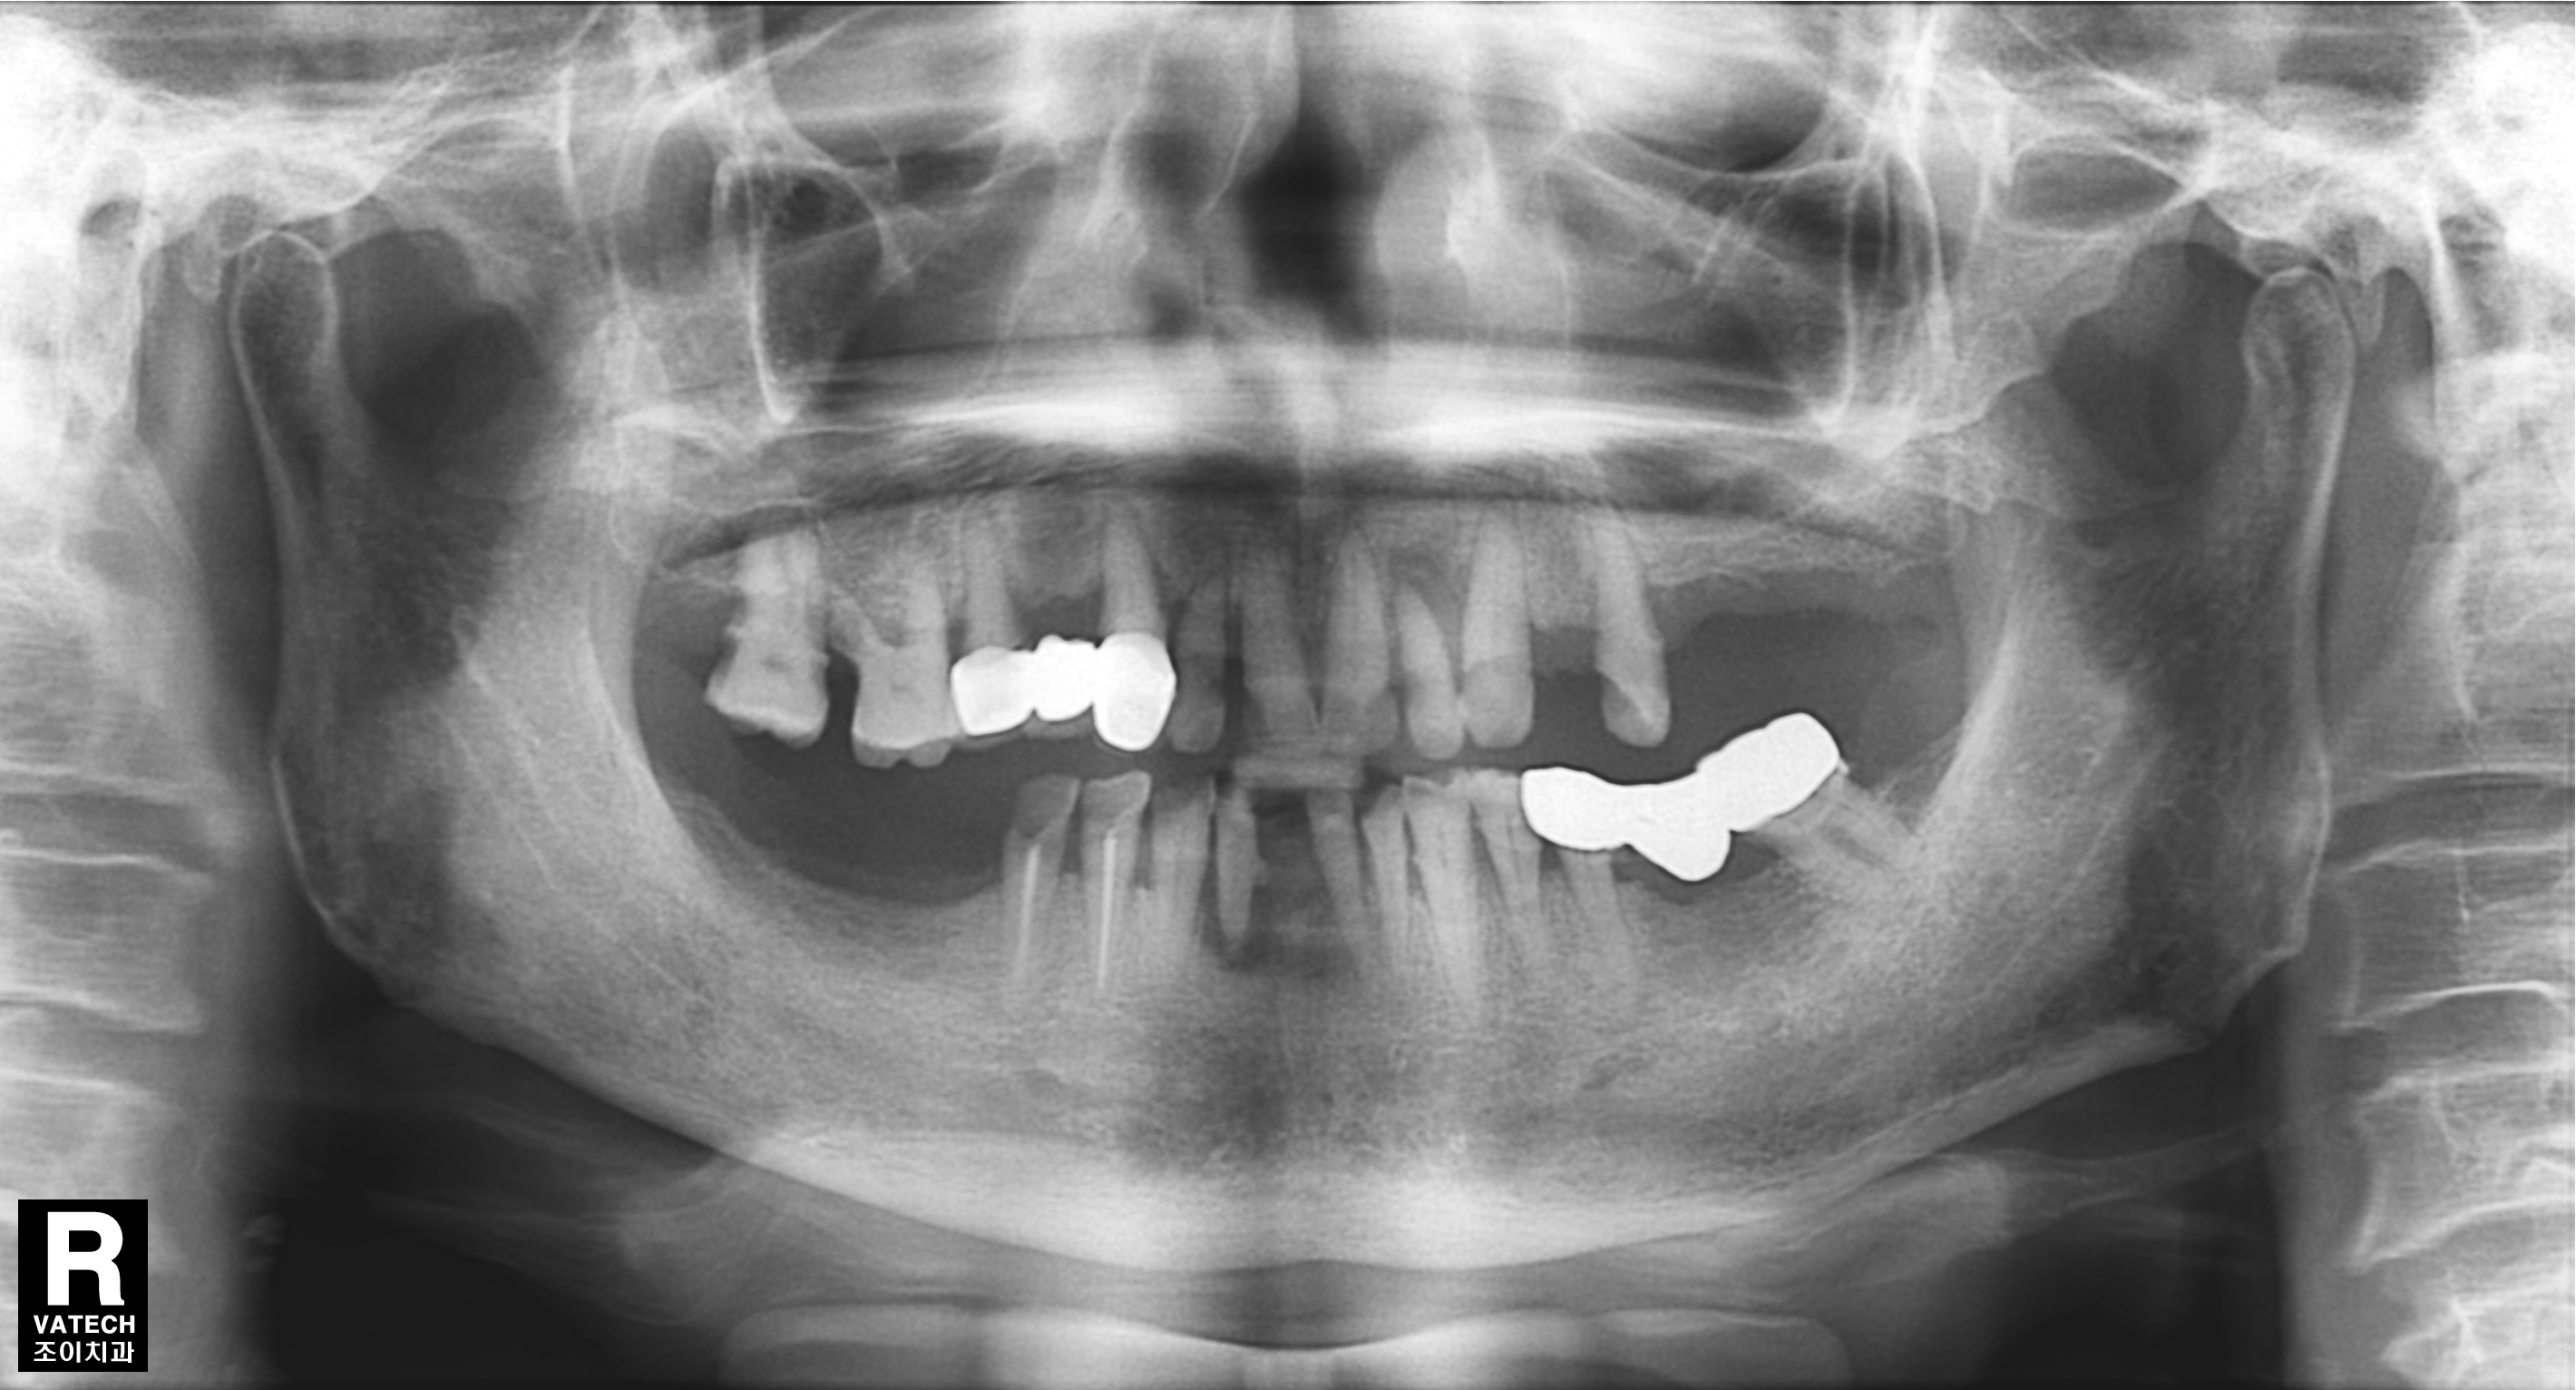

[임플란트] 제목 : 임플란트 지지 틀니

상악 임플란트 지지 틀니와 하악 고정식 보철의 만남.